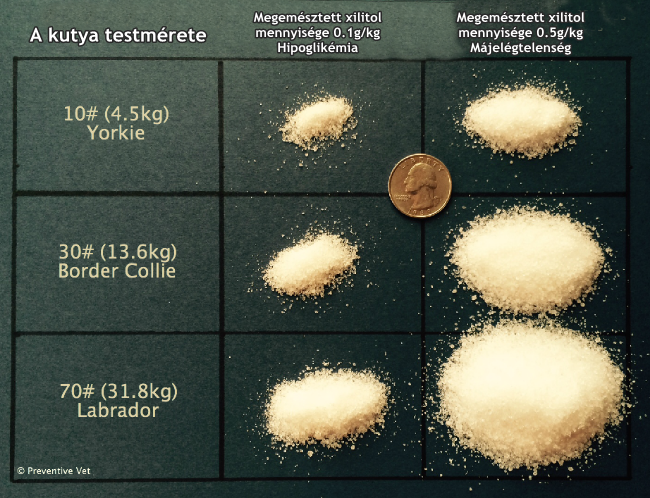

Fotó: preventivevet.com

Kutyák esetében 0.1 g/testtömeg kg feletti mennyiség is mérgezőnek számít, ennél magasabb mennyiség pedig májelégtelenséghez, potenciálisan életveszélyes állapothoz vezethet! Gyanú esetén ne habozzunk, ne az interneten kérdezgessünk utána annak, hogy mit tegyünk, hanem mielőbb forduljunk állatorvoshoz! Ha sikerül elérnünk telefonon még azelőtt, hogy beérnénk a rendelőbe, tartsuk be tanácsait, s csak abban az esetben próbálkozzunk hánytatással vagy gyógykészítmény adásával, ha kifejezetten erre utasított. (Az alacsony vércukorszint ugyanis rosszabbodhat a hánytatással, az elektrolit-háztartás kibillenésével.)